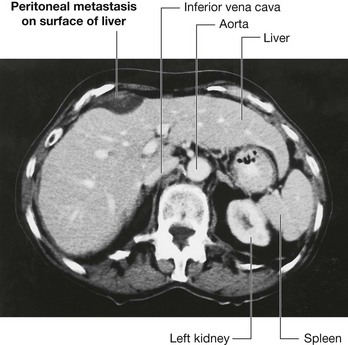

Peritoneal spread of disease

The large surface area of the peritoneal cavity allows infection and malignant disease to spread easily throughout the abdomen (Fig. 4.55). If malignant cells enter the peritoneal cavity by direct invasion (e.g., from colon or ovarian cancer) spread may be rapid. Similarly, a surgeon excising a malignant tumor and releasing malignant cells into the peritoneal cavity may cause an appreciable worsening of the patient’s prognosis. Infection can also spread across the large surface area.

image

Fig. 4.55 Peritoneal metastasis on the surface of the liver. Computed tomogram in the axial plane of the upper abdomen.

The peritoneal cavity can also act as a barrier to, and container of, disease. Intra-abdominal infection therefore tends to remain below the diaphragm rather than spread into other body cavities.